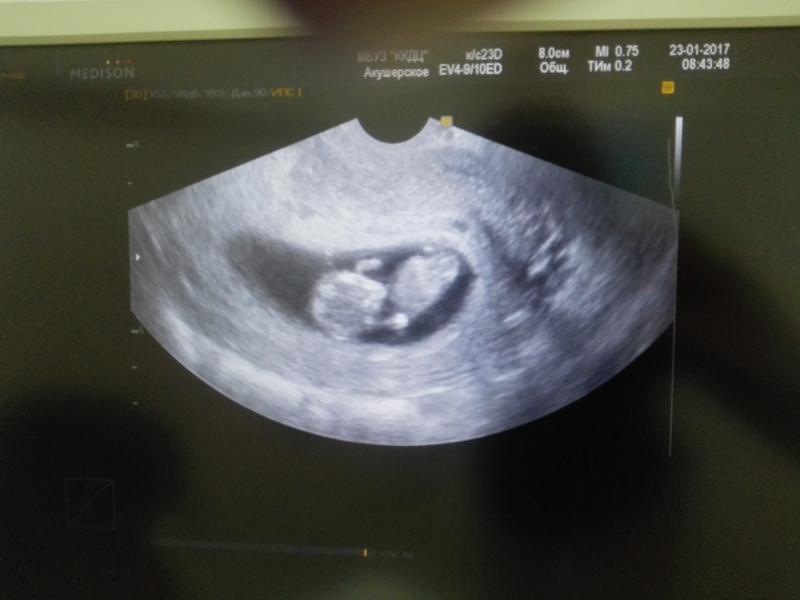

вот и первое фото нашего долгожданного малыша!!!мы ещё совсем маленькие...поэтому нам сказали прийти на повторный осмотр через неделю, тогда все расскажут и кровь возьмут.. Очень надеюсь что все будет хорошо!!!а пока сердечко бьётся и мы СЧАСТЛИВЫ!!!